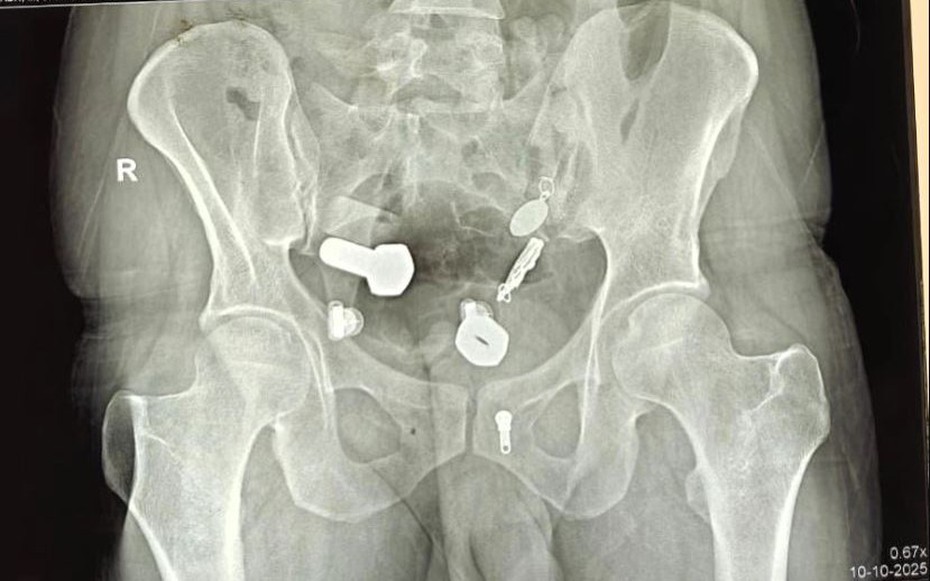

Các bác sĩ đã bị sốc khi kết quả chụp chiếu cho thấy một chiếc đồng hồ mắc kẹt trong thực quản của bệnh nhân, cùng với các mảnh sắt, đai ốc và bu lông mắc kẹt trong ruột già, theo như Need To Know đưa tin .

Hình ảnh chụp X-quang cho thấy khối vật thể kim loại kỳ lạ bên trong dạ dày của người đàn ông.